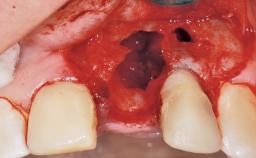

A 33-year-old female patient presented with an upper left central incisor that required extraction after a failed endodontic therapy. The tooth had been traumatized when the patient was a teenager and had undergone several endodontic treatments, including two apicectomy procedures. The patient was in good health and did not smoke. Clinical examination showed that the patient had a high lip line. In full smile, the gingival margins of the upper teeth were visible to the first molars. The gingival margins of central incisors 11 and 21 were only just showing. Examination of tooth 21 confirmed that the tooth was mobile and had hypererupted by 1 mm.

Socket Integrity | Damage to one or more bone walls |

Bone Volume | Damage to one or more socket walls |